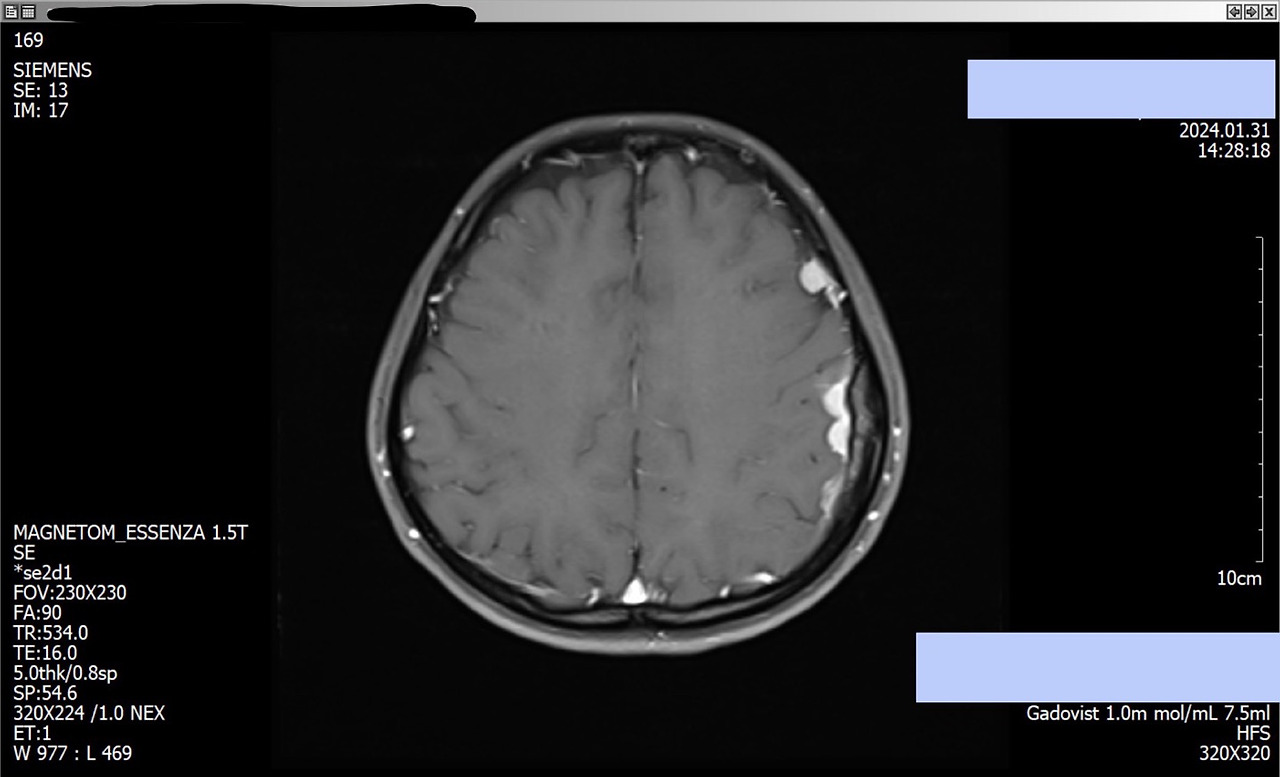

2024년 1월에 촬영한 뇌 MRI

나와 남편은 귤 종류의 과일을 까서 먹다가 이 사진을 떠올리곤 한다.

마치 귤 겉면에 붙은 흰색 귤락이 눈치 없이 두꺼워져 있는 듯한 형상이다.